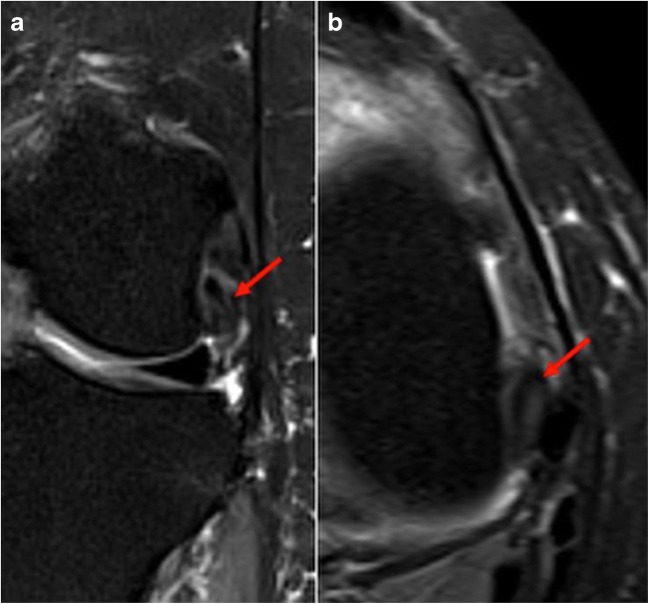

There is a wide range of diagnoses for chronic exercise-induced lower leg pain in athletes. Common etiologies include medial tibial stress syndrome (MTSS), chronic exertional compartment syndrome (CECS), tibial stress fractures, and popliteal artery entrapment syndrome (PAES) [13, 22]. A recent review of athletes presenting with exercise-induced leg pain found that 33% were diagnosed with CECS, 25% with stress fractures, 13% with MTSS, and 10% with nerve entrapment syndromes [13]. Other less frequently considered etiologies including saphenous nerve entrapment and tendinopathy of the popliteus should also be considered (Fig. 2a, b).

Fig. 2.

Coronal (a) and axial (b) T2 fat-suppressed images demonstrate thickening and increased T2 signal of the popliteus near its femoral insertion, indicative of tendinopathy.